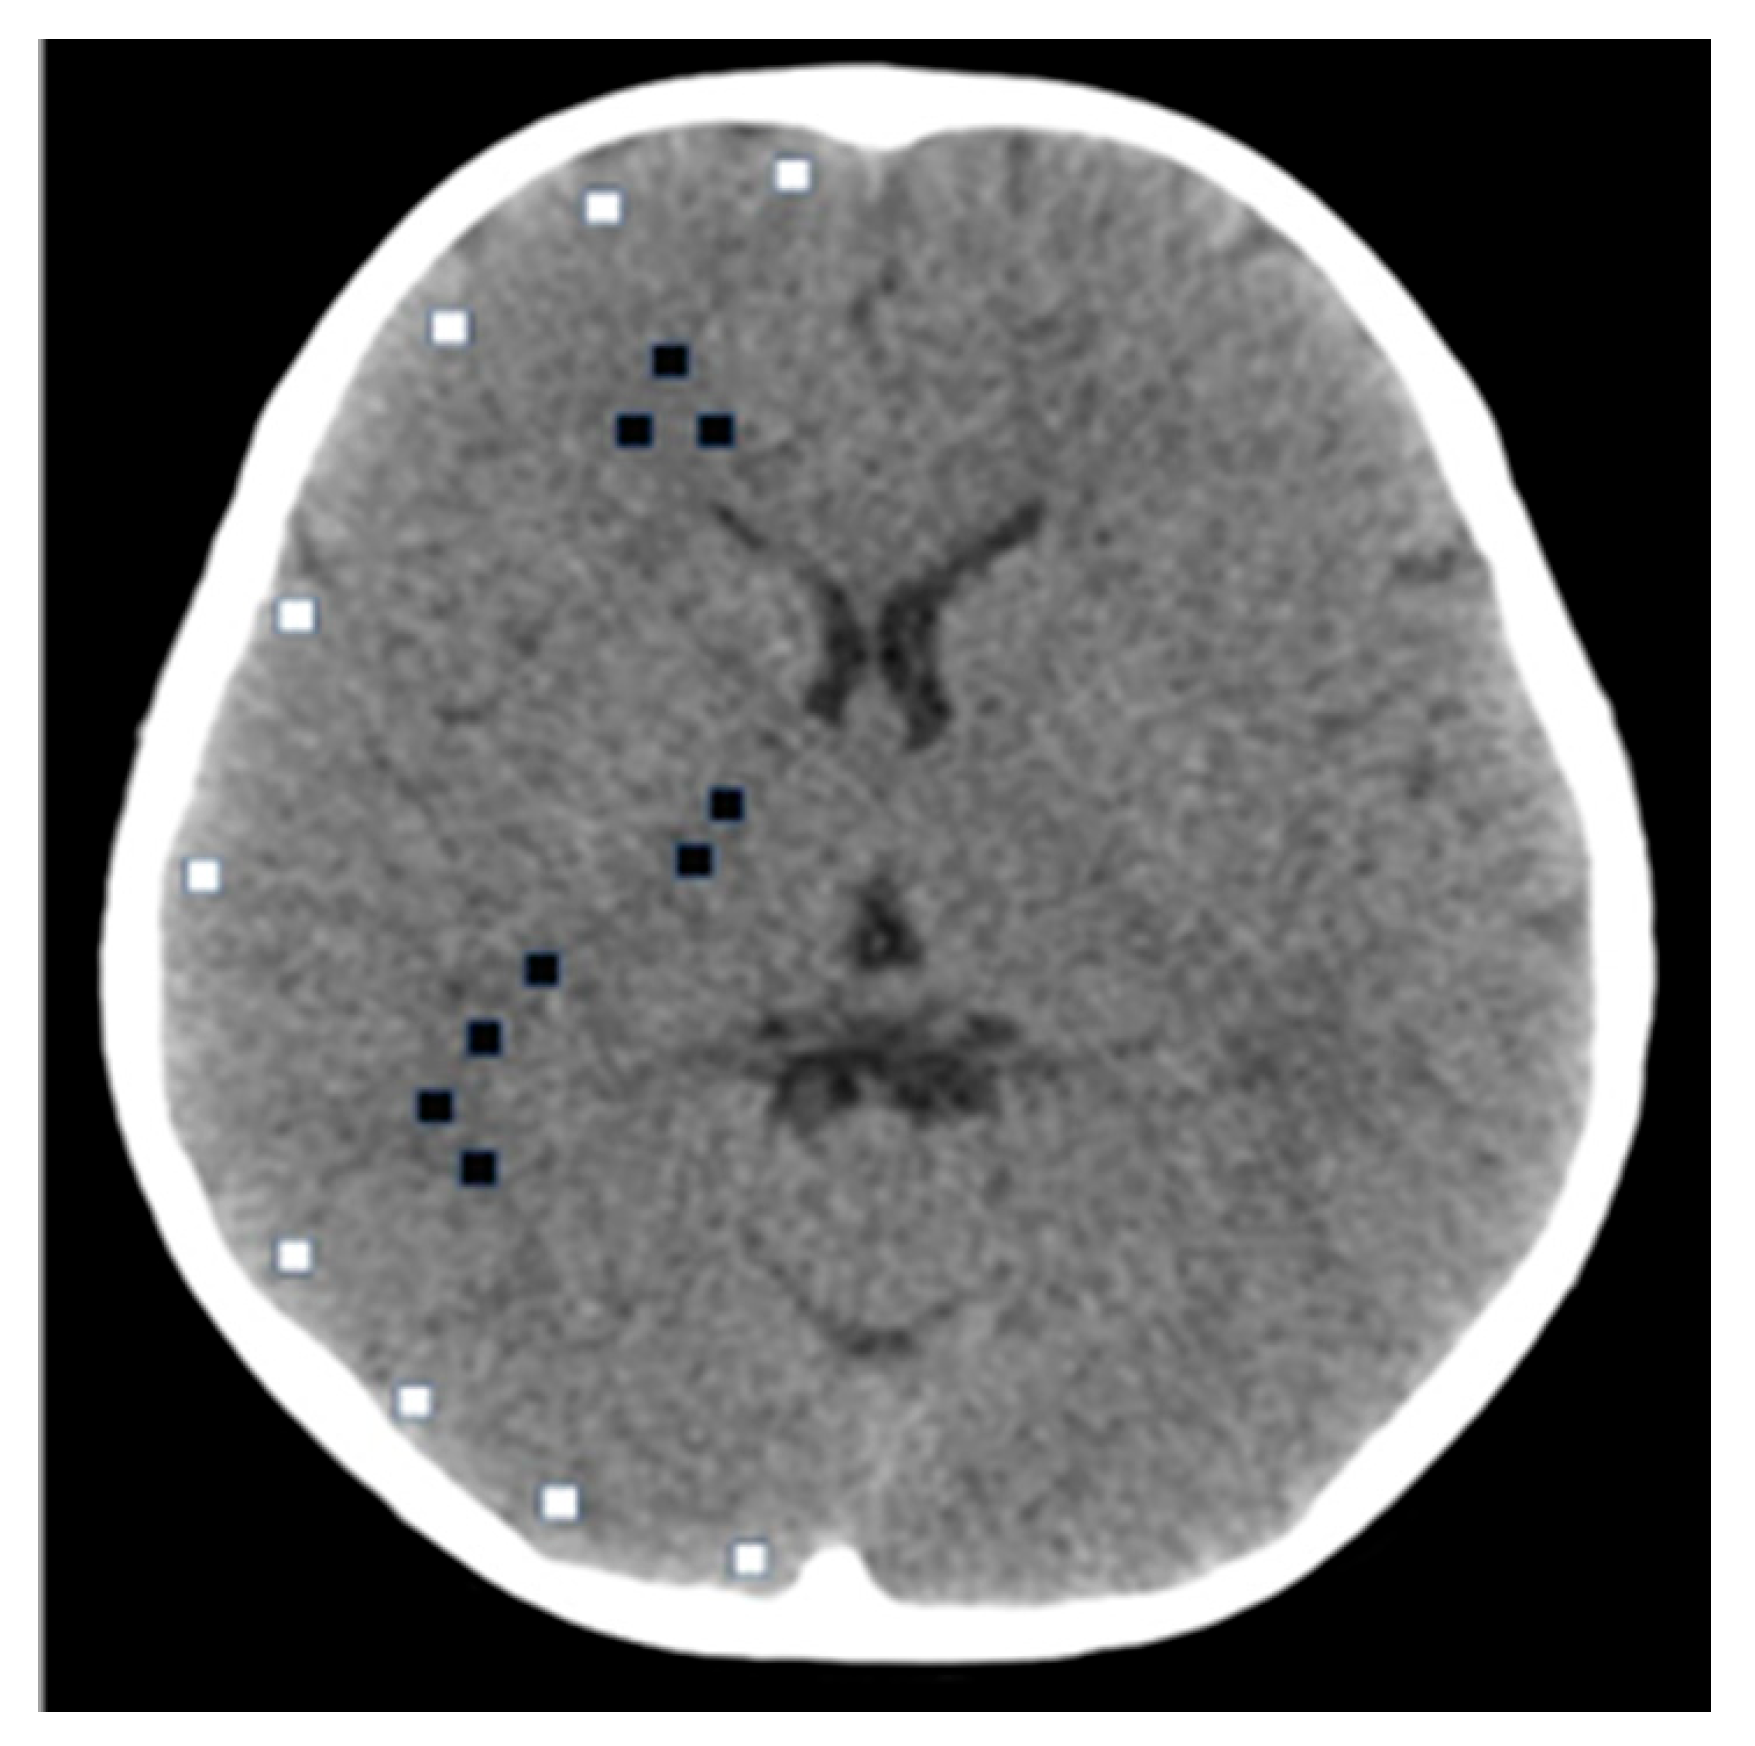

2.2. Study Population and Data Collection

2.3. CT Systems and Phantom Experiments

2.4. Image Quality Assessment